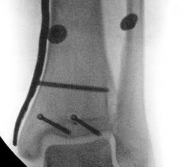

Fibular Fixation Strategy

The role of fibular fixation in distal tibia fractures remains a topic of academic debate, but in the context of intramedullary nailing, it is often a highly valuable adjunct. Plating the fibula restores the length of the lateral column and corrects rotational malalignment, effectively converting a highly unstable distal tibia fracture into a more manageable, length-stable pattern.

Image

Fibular fixation is typically performed prior to tibial nailing. An open reduction and internal fixation utilizing a one-third tubular plate or anatomic distal fibula plate is standard. By stabilizing the fibula, the tendency for the distal tibia to drift into valgus during nail insertion is significantly mitigated.